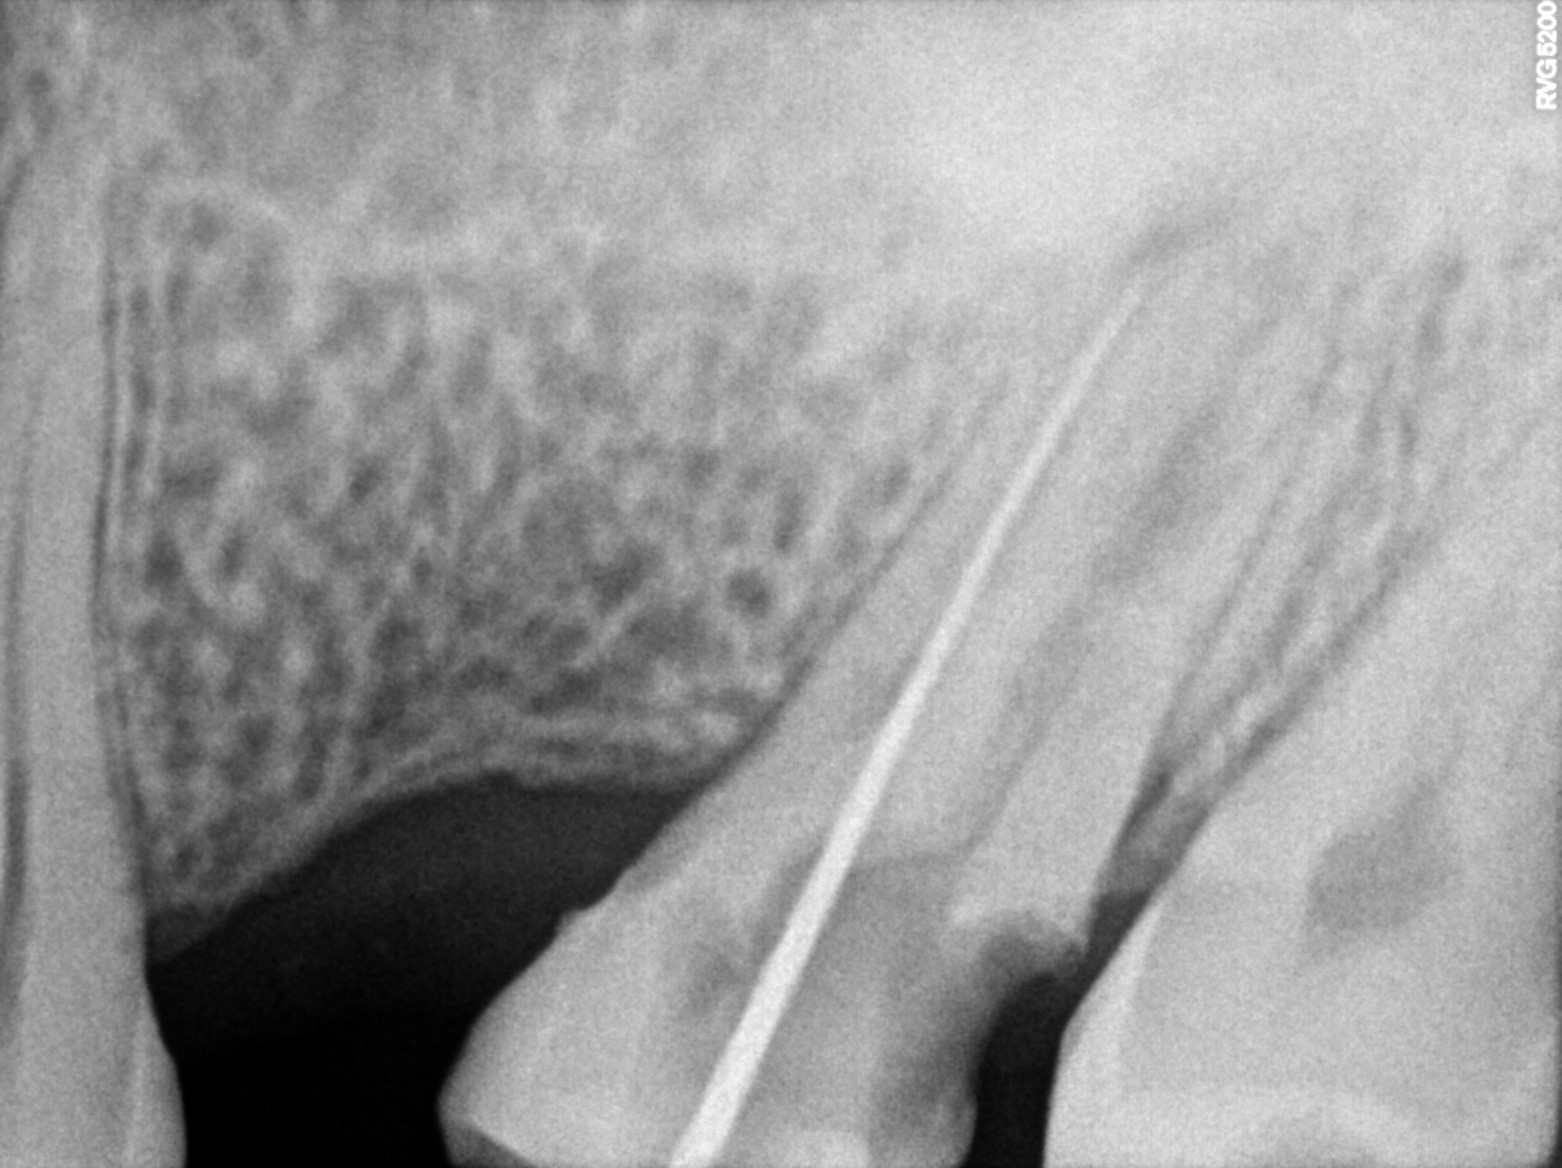

Dental Radiographs FHIR: DocumentReference · LOINC 24641-7

xray_1773248555_0.jpg

24641-7